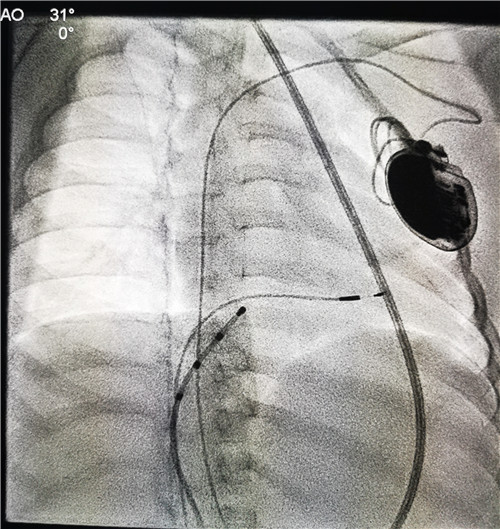

此时安安心肌酶显著增高、心脏增大、心功能下降,情况十分危急,甚至两度出现心跳骤停。儿童医学中心重症医学科和心血管团队积极抢救后考虑孩子存在病毒性心肌炎。为挽救安安生命,心血管团队袁勇华副主任医师为其紧急安装了临时起搏器,但临时起搏器取出后安安仍不能维持自主血压和心率,再次出现三度房室传导阻滞,只能再次进行临时起搏器治疗。

考虑到孩子年龄小,病情复杂,经多次全院大会诊以及学科大讨论以后,大家一致认为安装永久起搏器势在必行。手术前,儿童心血管专科联合儿童PICU、成人心内科、心胸外科、麻醉科、介入导管室共同商量探讨,制定了细致可行的手术方案。虽然在成人安装永久性心脏起搏器已经是一项非常成熟的技术,但对于年龄较小的安安而言,体格小、血管细、心腔小、起搏手术风险及难度远远超过成人,需要体积最小的起搏器。设备科了解情况后,高度重视,紧急调拨,第一时间从外省临时采购了符合安安的最小型号起搏器。

在充分应急预案和精细的手术流程设计前提下,手术在全麻下有条不紊地进行,介入导管室、麻醉科都派出了精兵强将团队,成人心血管专科和儿童重症监护室也为孩子保驾护航,最终手术顺利完成,术后起搏器参数均良好,安安经过恢复,一天比一天活泼开朗,病房里经常听到她稚嫩的笑声,看到她学走路、咿呀学说话的场景。